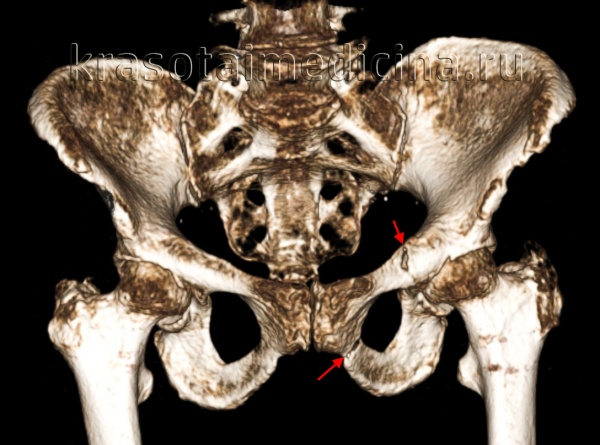

Для уточнения диагноза выполняют обзорную рентгенографию таза и рентгенографию поврежденного сустава в трех дополнительных проекциях. По возможности пациента направляют на КТ таза, поскольку эта методика позволяет более точно оценить тяжесть травмы и характер смещения отломков. Диагностическая ценность компьютерной томографии возрастает при повреждениях задней колонны и оскольчатых переломах.

Для определения типа перелома, оценки степени смещения, решения вопроса о необходимости оперативного лечения и выбора соответствующего доступа необходимо провести рентгенологическое исследование таза в косых проекциях и КТ. Существуют разные хирургические доступы к вертлужной впадине. Среди них доступ по Kocher-Langenbeck, подвздошно-паховый доступ, расширенный подвздошно-бедренный, модифицированный подвздошно-бедренный, по Stoppa, трехлучевой доступ, комбинированный переднезадний и чрескожный доступы.